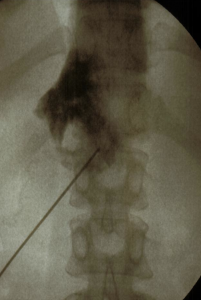

Abordaje posterior retrocrural clásico.

Con el paciente en decúbito prono se coloca una almohada bajo el abdomen. Puntos de referencia con el arco de fluoroscopia en AP se traza un triangulo cuya base está a nivel de L3-L4 con 7.5cm a cada lado y el vértice en la apófisis espinosa de L1. Las agujas se introducen a ambos vértices de la base del triangulo con angulación de 45º en dirección craneal hasta hacer contacto con el cuerpo vertebral de L1, después se aumenta la inclinación hasta 60º para atravesar tangencialmente el cuerpo vertebral hasta llegar al borde anterior del mismo, comprobándolo con el arco de fluoroscopia en lateral. Se inyecta contraste radiopaco (5ml) para ver la localización y difusión del contraste.